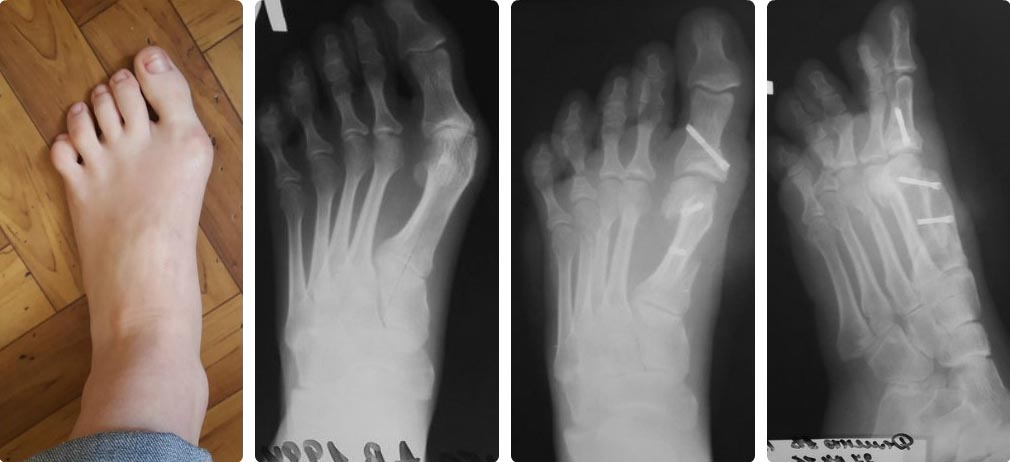

Прошу обсудить результаты операции!Всех кто в теме стопы)) Вопрос следующего характера 70-я юбилейная операция на стопах и хирурга понесло))) Оперировал девочку с выраженным египетским типом стопы. Год назад ей в другой клинике проведено оперативное лечение – операция Шеде с рецидивом. Диагноз: вальгусная деформация 1 п 2 степени. рецидив. Молоткообразная деформация 2,4 пальцев, подлежащий 3 палец. При осмотре омозолелость под головкой 1 плюсневой. Омозолеость по внутренней части основной фаланги, пальпаторно низкое расположение головки 4 плюсневой кости, глоловка прямо под кожей. Клинически этот же палец молоткообразный.2 палец тоже деформирован но не как молоток а не достигается подошвенное сгибание и вершина деформации как бы на уровне плюснефалангового сустава, плюс отклонен кнаружи. 3 и 4 пальцы как бы перекрещены На фото пальцы она расправила, как стала на стопу.План был такой scarf Akin + tilt up4, остеотомия основания 4 основной фаланги. Закрытая тенотомия разгибателей и поверхностного сгибателя 4п.В Итоге ,изначально, после завершения работы на 1 луче получилась хорошая квадратная стопа.После dmmo 4 имхо нужно было заканчивать…И еще очень сильно плантаризировал плюсневую ( чем может грозить?) Зачем- не скажу, сам не понял как так распилил. И это пол беды, далее что то так сказать увлекся радикализмом. Мысль изначально была такова- засчет dmmo устранить отклонение малых пальцев, и, учитывая что хоть на 3 ей плюсневой и нет деформации по снимкам она длинновата В итоге выполнил остетомии dmoo 2,3,4 плюсневых. Тенотомии 2,3,4 разгибателей. Остетотомию основной фаланги 4 пальца Итог- та же египетская стопа только с ровным пальцем((((! Чем может грозить? Давайте обсудим !

В самой по себе египетской стопе ничего особенного нет. Если длина первого пальца слишком сильно преобладает над длинами других пальцев, это может мешать при выборе обуви или восприниматься как косметический дефект. В данном случае вроде первый палец не такой уж длинный. Еще египетская стопа часто сопутствует избыточно длинной относительно латеральных первой плюсневой кости - одному из пусковых механизмов развития hallux rigidus. На дооперационном снимке первая плюсневая длиннее второй. Но там был hallux valgux, а это, своего рода, защитная реакция организма: при отклонении пальца кнаружи давление суставных поверхностей друг на друга снижается. После операции первая плюсневая укоротилась, но все-таки сохранилось преобладание ее длины над длинами латеральных плюсневых. Да еще вальгуса не стало. Можно предположить, что вероятность развития артроза в ПФС1 увеличилась. При этом плантаризация головки может оказаться и положительным моментом. Артрозу ПФС1 часто сопутствует не только слишком длинная М1, но и metatarsus primus elevatus. Так ли это в данном случае мы не знаем, боковой проекции под нагрузкой нет ни до ни после операции. Но если предположить, что головка М1 была расположена выше других, то плантаризация может сыграть положительную роль.

Вот снимок 2 день на перевязке. Кончик ногтевой фаланги засчет плантаризации м1 задран((!

Для меня основным показанием к DMMO чаще всего является наличие симптомов центральной метатарзалгии или боязнь получить центральную метатарзалгию при операции на относительно короткой М1. Особенно, если имеется бессимптомный натоптыш под головкой М2 (реже - М3). Здесь этого не было. Но в данном случае мы, по большому счету, имеем дело с отклонением кнутри не только первой, но и латеральных плюсневых костей. В такой ситуации нефиксированные остеотомии латеральных плюсневых костей могут помочь устранить отклонение кнаружи малых пальцев. В том числе, за счет смещения кнаружи головок центральных плюсневых костей. Так что, возможно, решение и было правильным. Время покажет. А насчет укорочения М2-3. Работ, доказывающих значение длинной М1 в развитии hallux rigidus много. А вот работ, показывающих, что после укорачивающей остеотомии М1 вероятность развития артроза сохраняется на прежнем уровне в случае, если одновременно были укорочены М2-3, мне не встречалось. Собственных подобных наблюдений у меня тоже нет. Готовая тема если не для диссертации, то для интересной статьи.

Формально, конечно, является. Но если подойти к вопросу не формально, а отталкиваться от опубликованных работ, то основным фактором риска рецидива является гипермобильность первого плюснеклиновидного сустава. Рентгенологически гипермобильности чаще всего сопутствует короткая М1 (здесь длинная), утолщенный медиальный кортикал М2 (в данном случае М2 совсем тонкая), закругленная (здесь плоская) суставная поверхность медиальной клиновидной кости и угол наклона суставной щели более 30 гр. (на дооперационной рентгенограмме у меня получилось больше, а на послеоперационной - меньше - разные проекции). Какой угол получился у Вас? Думаю, что по имеющимся данным вероятность рецидива за счет дальнейшего отклонения кнутри М1 крайне мала и показаний для артродеза первого плюснеклиновидного сустава здесь не было.